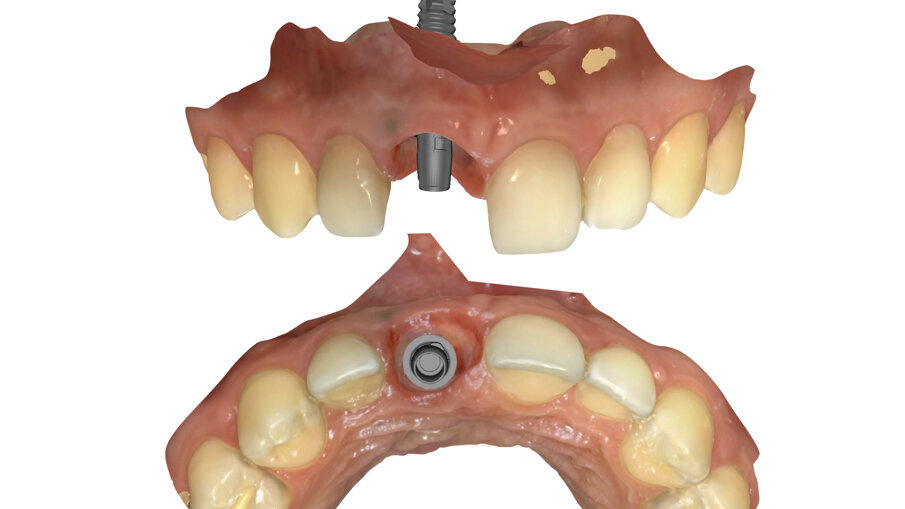

- posizione dell’impianto: quest’ultimo deve essere palatale rispetto all’asse dell’alveolo e centrale rispetto alla zona edentula (Fig. 9);

Fig. 9_Posizionamento ideale di un impianto in area estetica.

In questa fase finale si è proceduto a finalizzare protesicamente il caso seguendo una metodica di lavoro digitale “chair-side”. La chiave di questo step è la funzione “Copia e Ribalta” che il software protesico mette a disposizione, mediante la quale è possibile copiare la morfologia del dente 2.1 al fine di realizzare il dente 1.1 con la medesima forma (Fig. 28).

- Creazione della “Maschera gengivale”

Trascorsi quattro mesi, ad avvenuta osteointegrazione dell’impianto, il condizionamento dei tessuti appariva ottimale sia in termini di qualità dei tessuti sia in termini di volume rigenerato. I profili gengivali erano perfettamente armonici e naturali grazie al provvisorio (Fig. 29). A questo punto, dopo avere svitato il provvisorio dall’impianto, ho copiato con lo scanner intra-orale la posizione delle papille e della parabola gengivale. In tal modo, creando la cosiddetta “Maschera gengivale”, ho condiviso con il software le informazioni morfologiche necessarie per realizzare i manufatti protesici definitivi (Figg. 30, 31).

- Elaborazione modelli master e progettazione digitale

Ultimata la fase d’impronta ci si affiderà al software per la progettazione dei denti definitivi. Per cominciare è necessario disegnare la “Linea Base” sul profilo dei tessuti molli, evidenziando l’area entro la quale il software rileverà e creerà una corona protesica con il corretto profilo d’emergenza in grado di sostenere le papille e la parabola gengivale precedentemente condizionate. Successivamente dovrà essere disegnata la “Linea di copiatura”, selezionando il dente la cui anatomia si vuole replicare. Il software, elaborate le informazioni inserite, creerà il dente protesico definitivo, specchiando l’anatomia dell’incisivo centrale vicino sull’impianto. Gli strumenti digitali che il software mette a disposizione costituiscono un valido ausilio per perfezionare la forma dei denti protesici (Fig. 32).